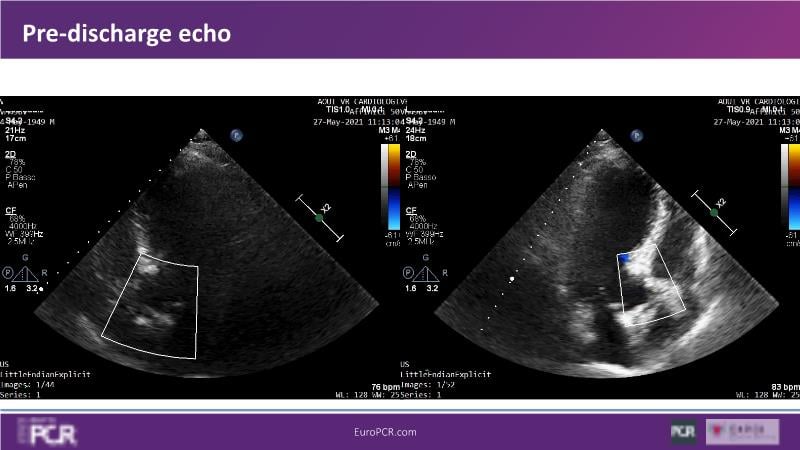

Discover the key factors to consider in selecting the optimal valve and implant technique for transcatheter aortic valve implantation (TAVI) to achieve optimal procedural outcomes. Gain insights into the impact of device choice and implantation technique on coronary access following TAVI and learn valuable strategies for tailoring your TAVI technique to complex scenarios, including bicuspid aortic valves, large and calcified anatomies, and ensuring coronary access.

- To appreciate the impact of device choice and implantation technique on coronary access after TAVI

- To learn how to tailor your TAVI technique to complex situations: bicuspid aortic valves, large, calcified anatomies and coronary access